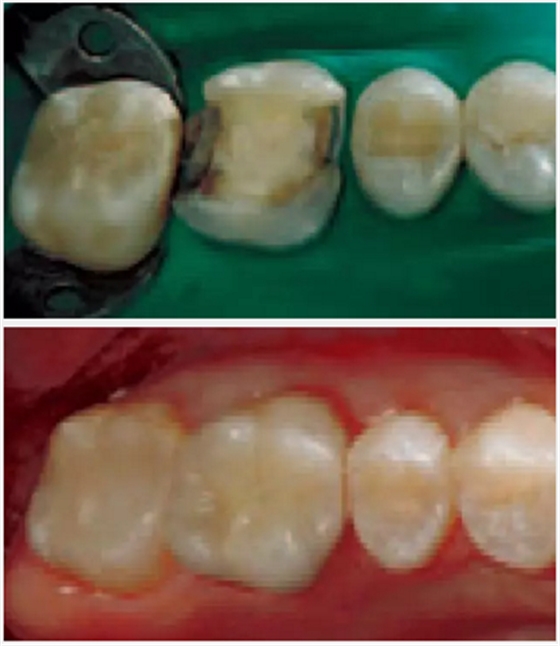

某些臨床情況,比如此前提,需要樹脂水門汀與強度和牙體顏色相匹配